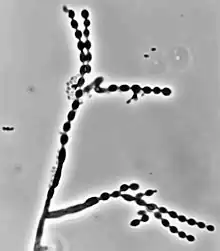

Colonies grow at a modest rate on Sabouraud dextrose agar.[1] The conidia of C. carrionii are unicellular oval-shaped spores that are distinguishable due to the presence of two lightly pigmented scars.[5][6] Conidia vary in length (1.5-3.0 × 2.0-7.5 μm).[1]

Its long conidiophores are similar to the genus Cladosporium, which comes from the Latin word "clado", meaning branched.[1] The genus Cladophialophora is distinguished from Cladosporium because in addition to chains of conidia, members of the genus Cladophialophora also produce phialides.[7]

Like many other black yeasts, C. carrionii is sensitive to temperatures above 37 °C.[5] It can be distinguished in culture by the presence of its urease enzyme hydrolyzing urea[8] and its inability to liquefy gelatin.[6][9] Altering temperatures or micronutrient levels such as calcium and phosphate affects whether C. carrionii is in the mycelial or muriform state.[2] The fungus transforms to muriform cells under conditions of temperature between 25 °C to 37 °C, 0.1 mM Ca2+, and a pH of 2.5.[7] It produces multiple conidia in long, straight chains that bud off the hyphae, with the youngest conidia farthest from the hyphae.[2] There is no sexual state known for C. carrionii.[5]